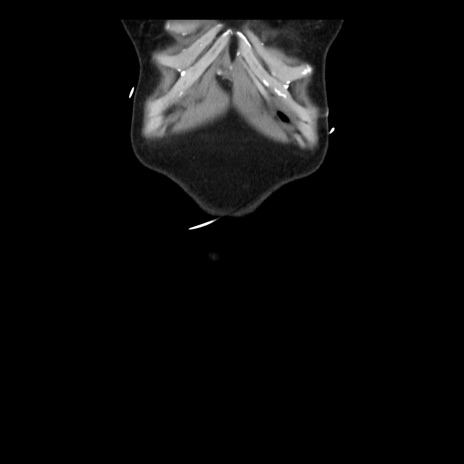

矢状断像